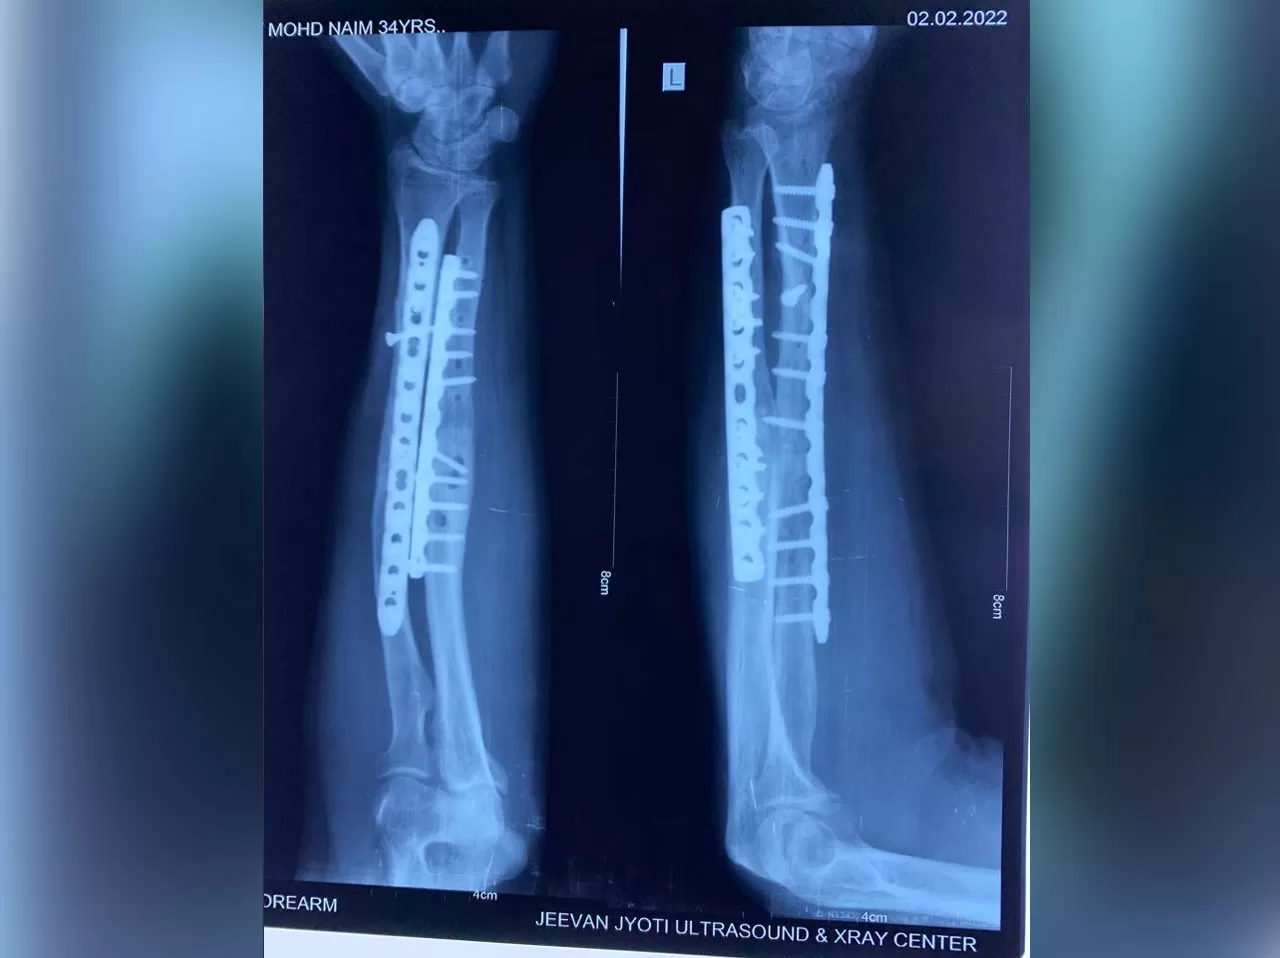

Mr. Naeem

Name: Mr. Naeem

Date of Operation: 5 Aug 2021

Age: 30 Years